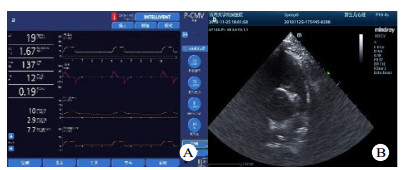

| A:为瑞士HAMILTON·G5呼吸机;B:肺动脉漂浮导管位置 图 1 本实验所用呼吸机及心脏超声机 Fig 1 Ventilator and echocardiography used in this experiment |